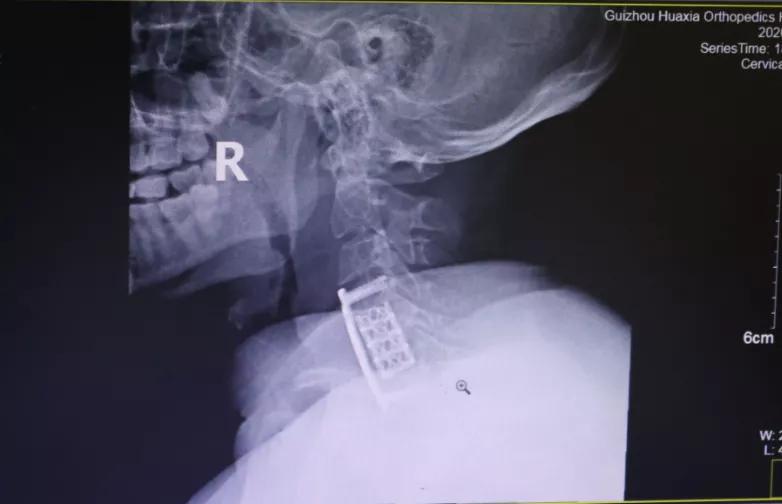

做了全面的检查后,胡阿姨被诊断为:颈椎病(脊髓型);颈椎间盘突出症 ;颈椎后纵带骨化症;肝功能不全 。患者诊断明确,存在明显手术指征,需行手术治疗,进行椎管减压,神经根松解,以阻止病变进一步发展,防止出现更加严重的双下肢瘫痪或大、小便功能障碍。

面对患者严重的病情,为使患者得到最佳、最快的治疗,12月18日,完善术前检查后,为胡阿姨实施了手术治疗。术后,疼痛、麻木等症状大大减轻。

“现在好了很多了,手术很成功。”12月28日,距离手术过去10天,胡阿姨恢复得还不错,心情也变好了。她表示,从医生到护士对病人都很热情,很暖心,谢谢大家。